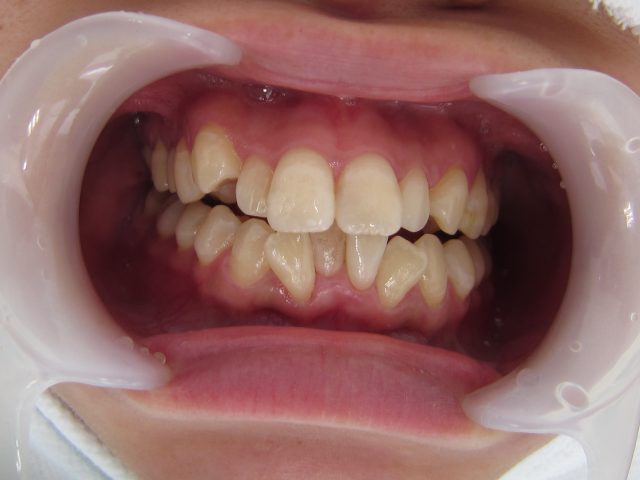

歯並びの矯正は、見た目の美しさだけでなく、健康面でも多くの利点があります。

歯並びが改善することで得られるメリット

最近注目の矯正治療法

どの方法が適しているかは、患者様のライフスタイルや目的によって異なりますので、歯科医とじっくり相談しながら最良の選択をしていくことが大切です。